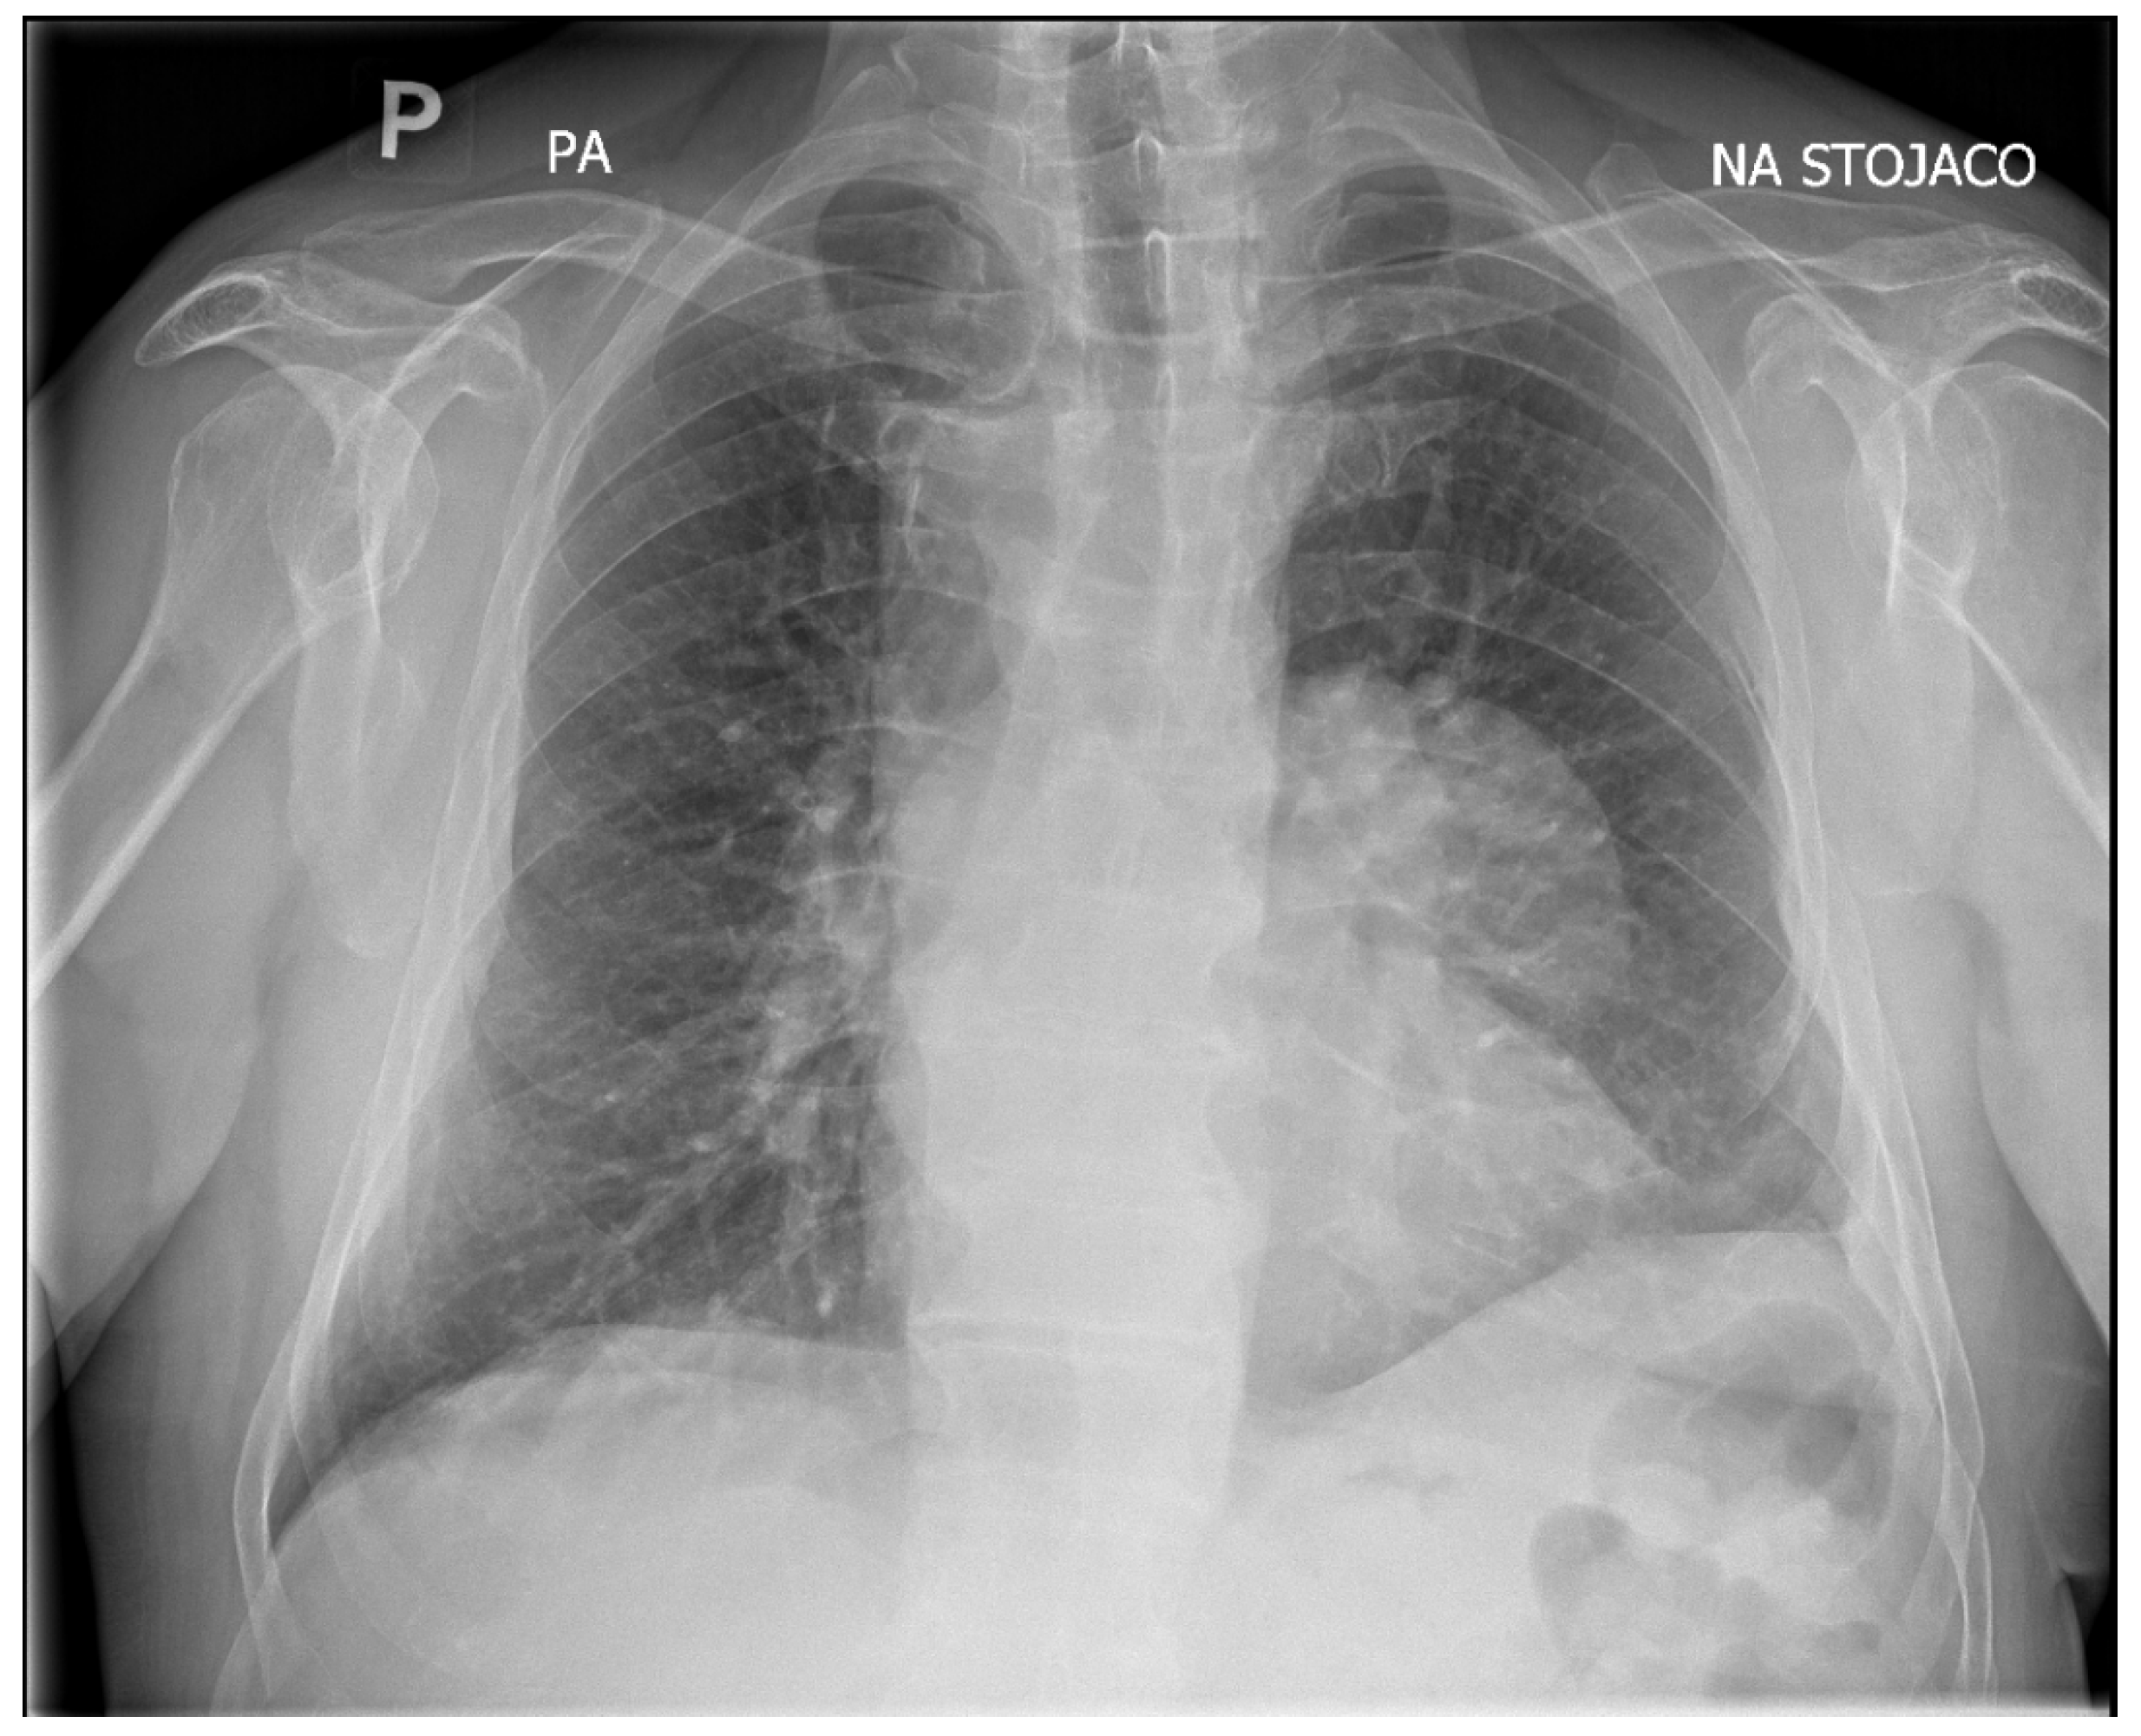

Due to the absence of medical contraindications, the patient was scheduled for elective surgical removal of the lesion. A thoracotomy was performed, with excision of the old scar and removal of the left fifth rib. The pleural cavity was obliterated, and a sharp detachment was performed within the upper lobe without interfering with the lower lobe. A thick-walled cyst measuring approximately 80 × 70 mm was visualized in the anterior mediastinum. This estimated visual dimension during thoracotomy, which is an approximate assessment, may be disturbed by the position of the cyst in the intraoperative field, hence the difference in relation to the dimensions from CT. This was the traditional surgical technique for mediastinal cystic lesions. The tissues were gently dissected and the lesion was enucleated using blunt dissection without rupturing the cyst wall. The operation had to be performed carefully so as not to rupture the cyst wall and cause contamination. After thorough examination, no focal lesions were found in the left lung.

The material was submitted to intraoperative examination (Figure 3). The cyst measured (ex vivo) 95 mm × 61 mm × 22 mm (Figure 4). The dimensions of the postoperative specimen are the ex vivo dimensions after removal and dissection of the cyst. The cyst flattened after fluid removal, explaining the difference in dimensions compared to the CT scan, which showed the cyst in situ, filled with fluid. Upon dissection, it had an uneven whitish internal surface with nodular thickening. Biopsies were collected for histological and cytological examination. The cyst fluid had not previously been aspirated for independent analysis. Cytological examination involved making a smear from the inner surface of the cyst wall, but only biopsies from the cyst wall, not from the nodular portion, were collected for histological examination. The cyst wall showed signs of necrosis and the presence of histiocytes and lymphoid cells. Cytological examination revealed structures consistent with protoscolex (Figure 5), suggesting Echinococcus spp.

Figure 3. Intraoperative image of the Echinoccocus spp. cyst removed from the patient’s anterior mediastinum.